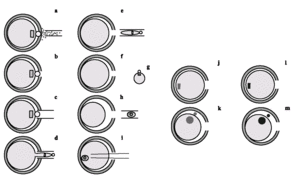

Figura 1. Transferência nuclear de espermatócitos secundários (ST2) para ovócitos MII não enucleados, seguido de activação eléctrica.

Figura 2. Transferência nuclear de um espermatócito primário (ST1) para ovócito MII não enucleado, seguido de activação eléctrica. Transferência nuclear do 1.o pseudo-glóbulo polar masculino para um ovócito MII não enucleado, seguido de activação eléctrica.

Figura 3. Transferência nuclear de uma célula folicular para um ovócito MII enucleado, seguida de activação. (A,B) Abertura de orifício na zona pelúcida (ZP) com Tirode ácido. (C-E) Enucleação em meio com citocalasina B. Aspiração do 1.o glóbulo polar (1PB: 1N2C) e do ooplasma subjacente, contendo os cromossomas femininos em metafase II (MII: 1N2C), libertando o carioplasto (F) e o ooplasto (G). (H) Transferência nuclear de uma célula folicular (FC, célula somática adulta do ovário, diplóide: 2N,1C) para o ooplasto. (I) A activação, em meio sem citocalasina B e com 5 µM ionomicina (ionoforo de cálcio), induz haploidização, com expulsão de um pseudo-glóbulo polar (PPB: 1N1C) e formação de um pseudo-pronúcleo haplóide (PPN: 1N1C). (J) A activação, em meio com citocalasina B, 5 µM ionomicina e 2.5 mM 6-dimetilaminopurina (6DMAP: inibidor da síntese proteica, que impede a citocinese), induz diploidização, formando-se um pseudo-pronúcleo diplóide (PPN: 2N1C) por não existir extrusão de um pseudo-glóbulo polar.

Figura 4. Haploidização. (a, b) A um ovócito dador efectua-se uma abertura na zona pelúcida (ZP) utilizando uma substância ácida contida numa micropipeta. (c, d) O ovócito é depois colocado numa solução (citocalasina B) que despolimeriza os microfilamentos submembranares (citosqueleto). Pelo orifício da ZP, aspira-se o 1.o glóbulo polar e uma pequena parte do citoplasma que lhe fica subjacente (Enucleação). Esta porção de citoplasma contém os cromossomas do ovócito. (e) Parando a aspiração e retraíndo a micropipeta, destaca-se o citoplasma aspirado. (f, g) Deste modo, obtém-se um ovócito sem material genético, ou citoplasto (f) e uma pequena porção de citoplasma com os cromossomas do ovócito, ou nucleoplasto (g). (h, i) Através do orifício da ZP, uma célula diplóide somática adulta (feminina ou masculina) é microinjectada (Transferência Nuclear) no interior do citoplasto. (j, l) Deixando o citoplasto algumas horas em repouso, os cromossomas da célula somática (j: feminina; l: masculina) condensam-se e adquirem a conformação natural do ovócito, ou seja, evoluem para metafase. (k, m) O citoplasto é activado quimicamente (ionoforo de cálcio), induzindo a libertação para o exterior de metade dos cromossomas da célula somática, pelo que no citoplasto apenas ficam 23 cromossomas, femininos (k) ou masculinos (m).